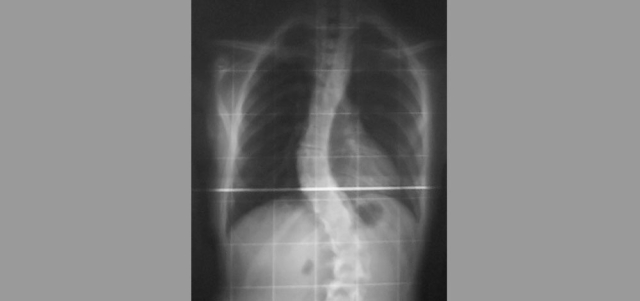

«شيماء» تعاني تشوهات في العمود الفقري

تعاني المريضة (شيماء) (19 سنة ـــ من جنسية دولة خليجية)، تشوهات في العمود الفقري، وتحتاج إلى جراحة عاجلة لمنع تدهور حالتها، تبلغ كلفتها 50 ألف درهم، لكن الإمكانات المالية لأسرتها لا تسمح بتأمين هذا المبلغ، لذا يناشدون أهل الخير مساعدتها في توفير كلفة العملية.

وأوضح التقرير الطبي الصادر من مستشفى الشيخ خليفة بن زايد في عجمان، أن «المريضة تبلغ من العمر 19 عاماً، وتم تشخيص حالتها من قبل الأطباء المختصين في عيادة العظام، وتبين أنها تعاني انحرافاً خلقياً في العمود الفقري، وتحتاج إلى تدخل جراحي لتصليح التشوه ومنع تدهور الحالة»، مشيراً إلى أن هناك طبيباً مختصاً في مثل هذا النوع من الجراحات، سوف يزور المستشفى الأسبوع المقبل.